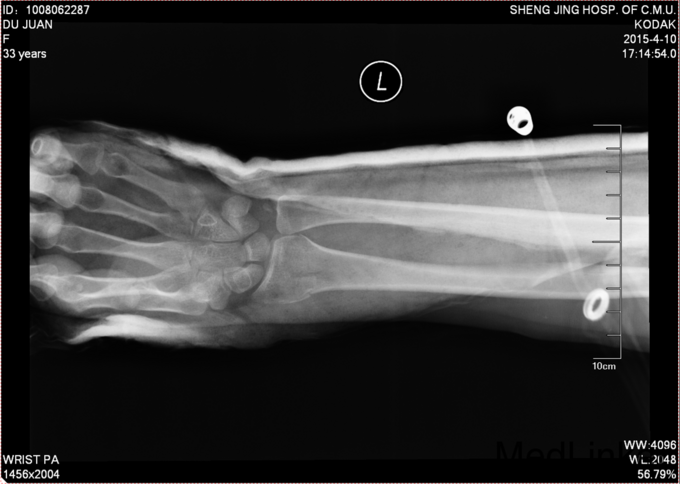

术后给予患者止疼消肿等对症治疗,石膏固定后2周后给予复查腕关节正侧位DR,位置良好,更换功能位短石膏。